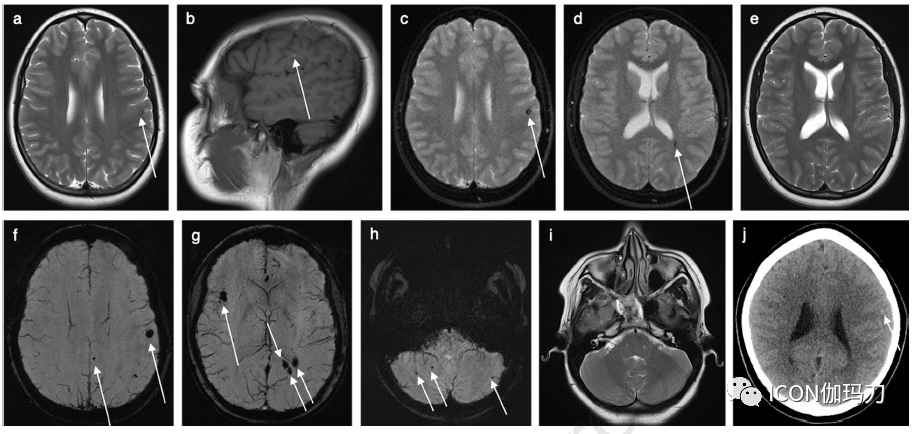

图2、16岁女性患者,双侧下部鼻侧视野 缺损,疑似颅内病变。轴位T2-WI (a)示左侧额叶小的高信号病灶,被低信号环包围(箭头),对应有矢状位T1-WI高信号(b)(箭头)。(c)轴位DWI (b0)显示相应的局灶信号缺失,即在与(a)和(b)(箭头)相同的位置出现了“开花”伪影。在毗邻左侧侧脑室枕角的脑室周围白质可见进一步低信号区域(d)(箭头),但但在同期的轴位T2-WI没有同时发生的信号异常 (e)。患者再行轴位SWI显示在整个大脑的几个区域有“开花的”伪影子(箭头)(f-h)。然而,相应的轴位幕上T2-WI(i)显示未见低信号病灶(h)。SWI时获得的轴位头部CT (j)在左侧额叶的同一位置SWI显示一个微妙的局灶高密度(箭头)(a)和(b)。(a-j)的影像特点符合多发CCMs和在多个CCMs的情况下,SWI值加强,而在其他MRI序列上不可见,或者在CT上显示不清。

图3、所选轴位神经影像来自12岁男性,有左额CCM伴癫痫发作。(a)头部CT显示左侧额叶有偏心性钙化的高密度区域。(b) T2-WI和(c) T1-WI显示左额叶特征性小叶“爆米花”表现,信号强度不均,反映了血红蛋白破裂的不同阶段(高铁血红蛋白引起中央高信号,含铁血黄素沉积引起低信号边缘包围)。(d) SWI在同一位置显示显著的“开花”伪影,这是CCM的典型特征。靠近或累及大脑皮层的病灶可能是潜在的癫痫发作病灶(致癫痫灶)。对患者服用药物无法控制的癫痫灶进行显微外科切除,术后治愈。随访 MRI未发现残留病灶。

图4、所选MRI来自10岁女性,有2年偏身肌张力障碍病史。(a)轴位T2-WI显示右侧基底节区大的异质性病变,中央信号强度混合,符合巨大CCM。(b)轴位T2*-WI较好地显示周围低信号含铁血黄素边缘,并在右侧额叶胼胝体膝前部进一步发现小的点样CCM。(a)同期轴位T2-WI未发现相应的信号异常,进一步加强了SWI对CCM的诊断价值,特别是应积极寻找可能伴巨大CCMs的小的/微小的点样病灶。(c)冠状位T1-WI进一步显示巨大CCM的内部异质性和部分囊性。(d) (冠状位重建)Willis环飞行时间血管造影显示病灶没有动脉供血。进行DTI是考虑到巨大CCM位于高度重要功能区域:(e)斜冠状位和(f)轴向成角视图显示右侧皮质脊髓束及其与巨大CCM的关系。选择这些影像是为了更好地突出白质束及其围绕病灶的偏移,而不是显示病变本身。患者有家族性海绵状血管畸形(FCCM)家族史,KRIT1突变阳性(CCM1,常染色体显性遗传)。手术切除巨大CCM后,肌张力障碍明显改善。对较小的右侧额叶CCM进行SRS治疗,在随访影像中保持稳定。